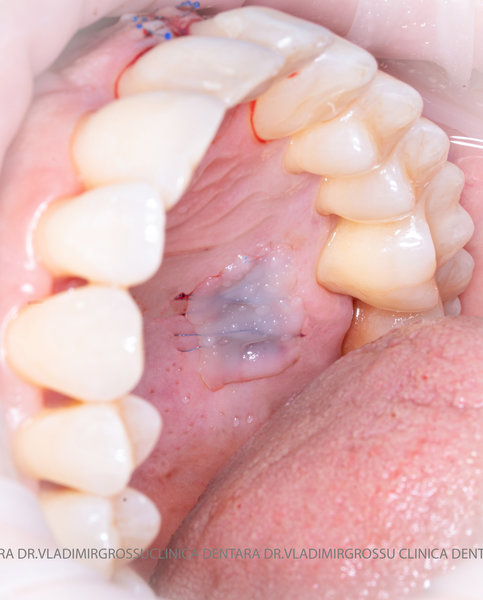

Aditia gingivală este o procedură chirurgicală ce corectează diverse probleme estetice și funcționale, cum ar fi recesiunea gingivală. În implantologia modernă, aditia de țesut moale este utilizată aproape în fiecare intervenție de inserție a implantului dentar pentru a asigura un aspect estetic natural și o bună integrare a implantului în cavitatea bucală.

Adiția osoasă are un rol crucial pentru poziționarea corectă și stabilă a implanturilor dentare. Clinica stomatologică Dr. Grossu din Chișinău promovează o abordare chirurgicală estetică și predictibilă, adaptată fiecărui caz în parte.